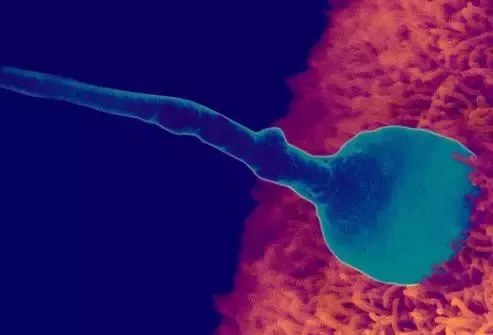

受精卵吸收母亲提供的营养物质,细胞迅速分裂、增殖和发育。一些细胞形成胚胎并发育成胎儿;细胞的另一部分形成胎儿膜、羊水、脐带和胎盘,称为胎儿附属物,以确保胎儿的发育。

一个月:它标志着胚胎期的开始。身体长约0.2厘米,重约1克。受精卵裂变形成桑椹胚,并继续分裂成囊胚和着床。每个月,新生命的生长速度比任何时候都快,比受精卵高一万倍。动脉和静脉已经形成,并有血液流动;大脑、肾脏和消化道已经开始形成;脐带已经开始工作;心脏已经形成并开始跳动。